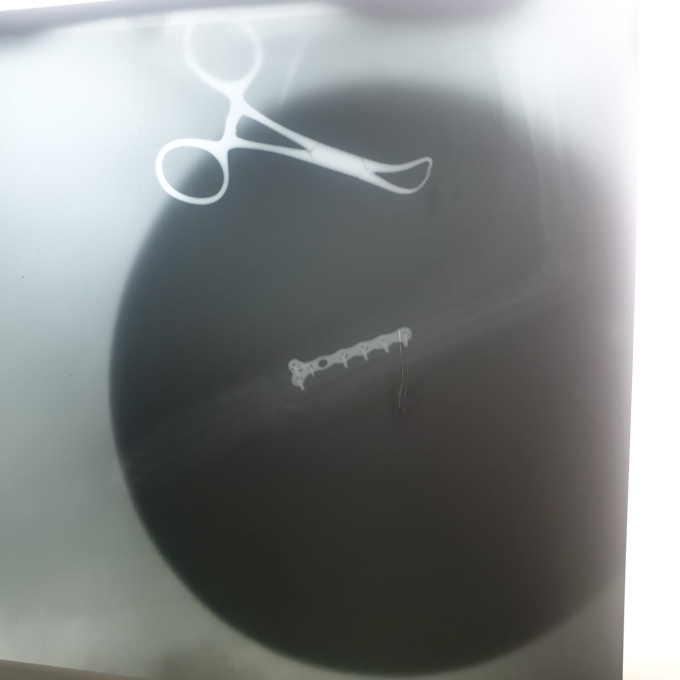

The vet spoke a little English, and took us into his room and showed us the implant. He said a bandage would not be necessary as the plate would hold everything together. He said the stitches would come out in two weeks, but that any vet could do this. He wanted to x-ray her again in two months to see that it had healed correctly. Explaining that we might not be here in two months, but that we could take her to another vet, he seemed happy enough. He took Aimee off us, telling us to return at 2pm.

Soon enough, we were back at the vets. He showed us into another room where Aimee lat stretched out, still asleep. He told us we could wait for half an hour or so until she had woken up and then take her. Contrary to what he had said, her leg was encased in a huge bandage, even larger than last time. He told us that the incision was quite large, and that she only needed the bandage for a week to protect it. With the help of google translate, we got some wormer for her and he gave us her medication. The assistant loaded her into her bag, where she lay and growled at us all, then we payed him 7000mxp for the surgery, before leaving with the cat and a bag containing her X-rays.